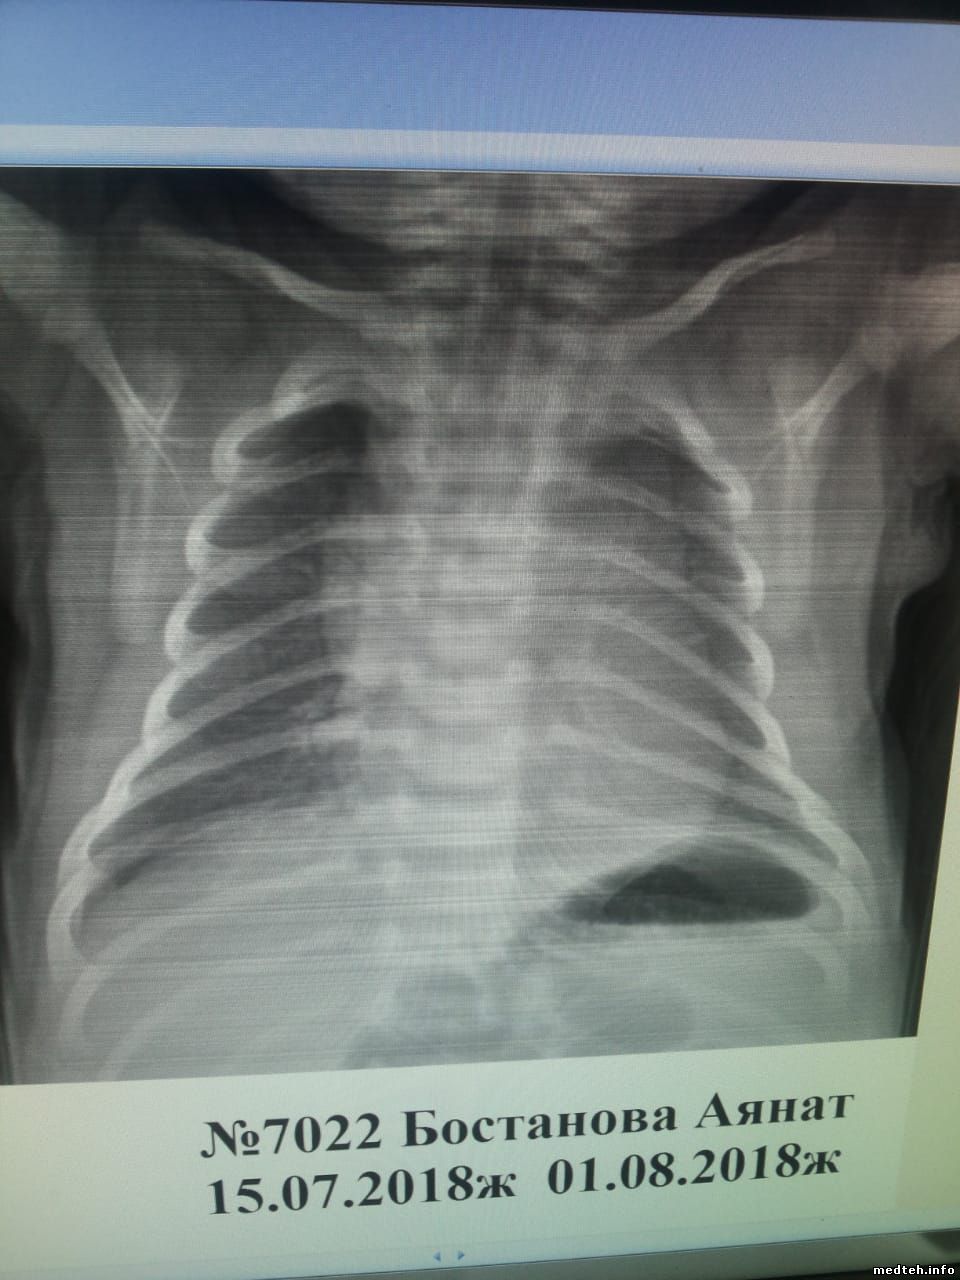

Здравствуйте дорогие форумчане, аппарат medonica blue-dr штатив потолочный, стойка детекторная, после хорошего скачка напряжения появились полосы на снимки, если раньше помогало полное выключение и перезагрузка то после последнего скачка напряжения полосы остались, ошибок никаких не показывает, сталкивался с похожей проблемой на филипсе помогла каллибровка трубки с детектором, но с данным аппаратом увиделся в первые мануал который имеется это строго описание работы и ошибки, кто сталкивался с данным аппаратом подскажите в чём может быть проблема, если в калибровке то как каллибровка делается на данном аппарате, за любую помощь буду очень благодарен фото прилагаю.